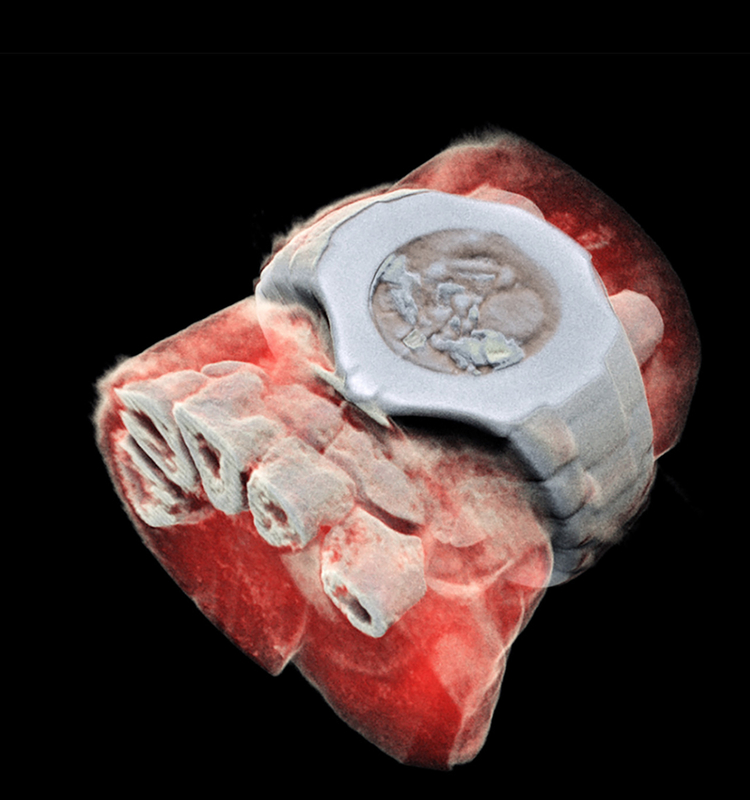

Сканер компании Mars Bioimaging позволяет получать цветные объемные изображения костей и мягких тканей. Получаемые трехмерные изображения четче и точнее привычных монохромных рентгенограмм, что поможет врачам в диагностике.При получении традиционных рентгеновских снимков лучи проходят сквозь ткани и регистрируются на специальной пленке. Такая рентгенограмма — по сути, проекция трехмерного объекта на плоскость, из-за чего врачам нередко требовалось сделать как минимум два снимка в разных проекциях, чтобы, к примеру, установить серьезность перелома, очертить границы раковой опухоли или диагностировать аномалию сосудов.

Принцип получения изображения не менялся, технология затрагивала только способ фиксации результатов. Новая разработка основана на том, что рентгеновские волны разной длины при прохождении через различные материалы затухают не одинаково быстро. Сенсор, измеряющий коэффициент затухания, дает информацию о свойствах среды. Затем (и в этом коренное отличие от традиционного аналогового рентгена) в дело вступают алгоритмы, генерирующие полноценное трехмерное цветное изображение. Если при использовании традиционной техники плохо пропускающая лучи кость вызывает такое же затемнение на снимке, как вдвое больший слой жира, то новый метод позволяет различить эти два случая, так как разные длины волн в костной и жировой ткани затухают по-разному. В результате на «цветном» снимке детально видны кости, мышцы, жировые слои и маркеры заболеваний, а само изображение больше напоминает модель из электронных атласов по анатомии.

Новое оборудование в Mars Bioimaging называют «аппарат спектральной компьютерной томографии». Его основой стал чип Medipix3, изначально разработанный в CERN для Большого адронного коллайдера. Medipix способен распознавать частицу, попадающую на каждый пиксель сенсора. Благодаря этому он обеспечивает высокую четкость и контрастность изображения.В рентгеновском аппарате Medipix3 был дополнен вычислительными алгоритмами, которые конвертируют данные с детектора в итоговое изображение. Цвета представляют разные уровни энергии рентгеновских лучей, зафиксированных детектором.